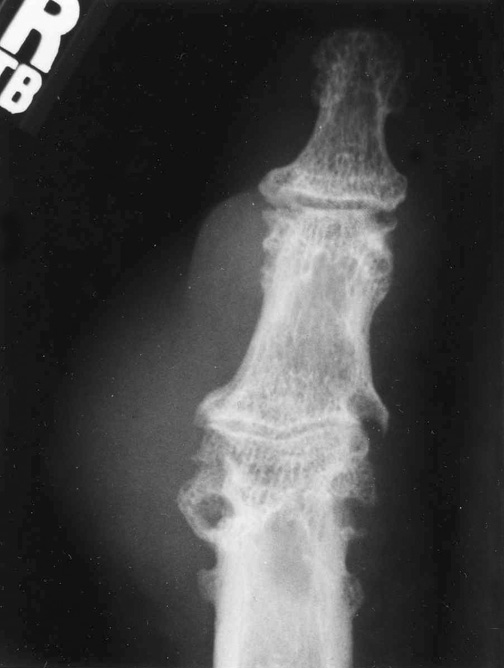

| Рентгенография суставов | Визуализация суставов с помощью рентгеновских лучей. | Обнаружение характерных изменений в суставах (тофусы, эрозии). Не позволяет диагностировать подагру на ранних стадиях. |

Рентгенографию назначают на начальных этапах заболевания для исключения других патологий, вызывающих воспаление суставов. При подагре значительных изменений не наблюдается. Только рентгеновские снимки, сделанные при хронической форме заболевания, могут помочь в постановке диагноза.

Некоторые упоминают о необходимости рентгенографии, которая позволяет выявить изменения в суставах, вызванные заболеванием. Другие пациенты рассказывают о процедуре артроцентеза, когда из сустава берется жидкость для анализа. Этот метод считается наиболее точным, так как позволяет обнаружить кристаллы мочевой кислоты. Важно, чтобы диагностику проводил опытный врач, который сможет интерпретировать результаты и назначить соответствующее лечение.